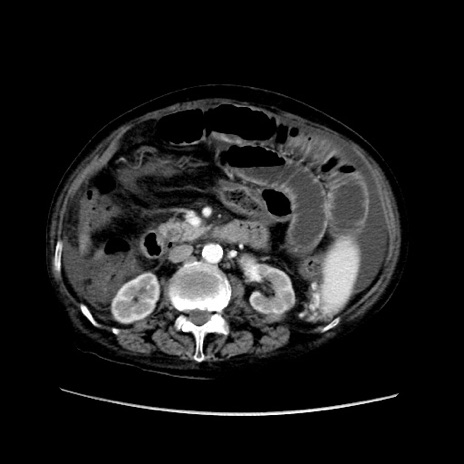

症例31(横断像)

【症例】80歳代 女性

【主訴】腹部膨満感

【現病歴】他院にて肝硬変にてフォロー中。1週間前から便秘、腹部膨満感、臍部腫瘤あり受診となる。

【既往歴】肝硬変

【身体所見】腹部膨隆あり、皮膚変化なし、疼痛なし。

【データ】WBC 4600、CRP 0.25